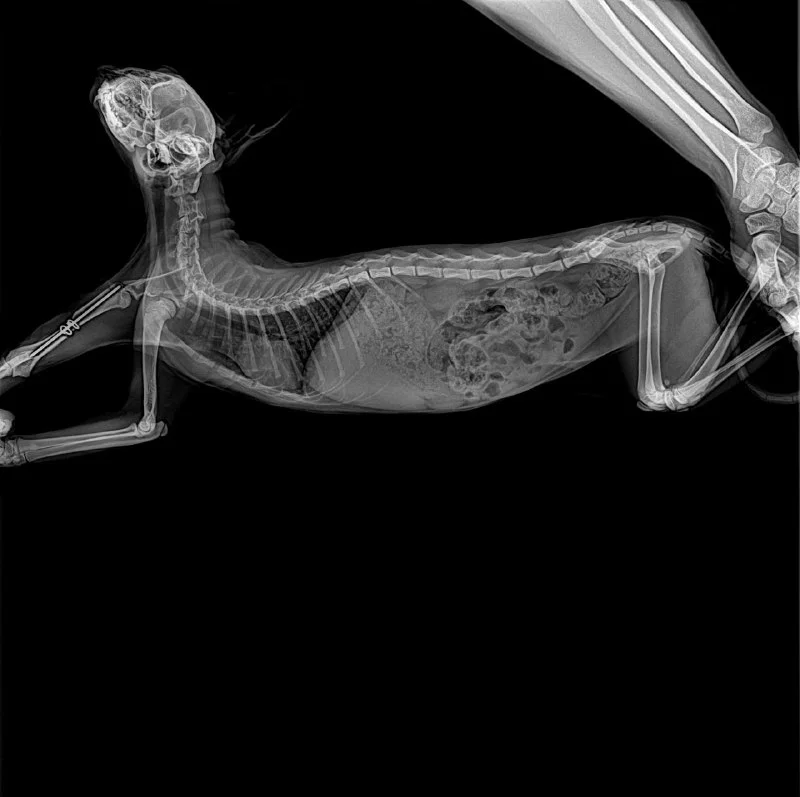

У меня грустные новости от Зайки…

В Лапке ниже локтя чувствительности совсем нет, значит был перебит нерв… 💔

Вчера сняли бандаж, и вот такая печаль.

Спица вставлена идеально, вопросов нет. Но на первый вопрос от другого врача «а была ли чувствительность изначально?» я не смогла ответить… потому что как оказалось, ее проверяют до седации, наш доктор хирург изначально этого не сделал.

В вчера сделали повторный рентген - в другой клинике, в Ларнаке, там где снимали повязку.